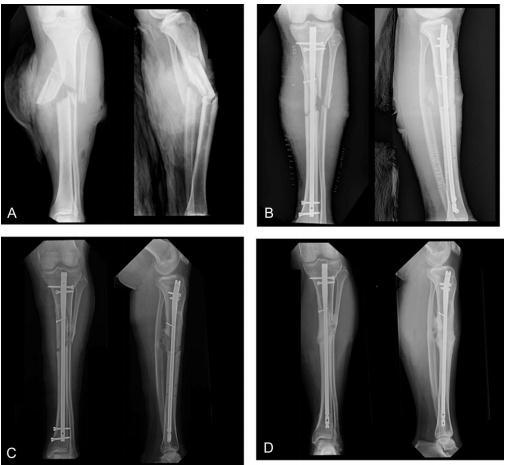

图1 A、B 24岁男性,Ⅲ度胫骨开放性骨折;C术后161天拆除远端螺钉行动力化治疗骨折不愈合,RUST评分为5分;D术后334天骨折愈合,RUST评分10分

骨折延迟愈合或不愈合是胫骨骨折常见的并发症,而且治疗也较困难。文献报道:髓内钉治疗胫骨骨折的不愈合率可达5%~17%(闭合性)和40%(开放性)。髓内钉动力化和更换髓内钉是常见的二次手术干预手段。动力化是指拆除髓内钉近端或者远端的静态交锁螺钉加强骨折端微动,从而促进骨折愈合(图1)。更换髓内钉包括移除髓内钉、扩髓和植入更粗的髓内钉。